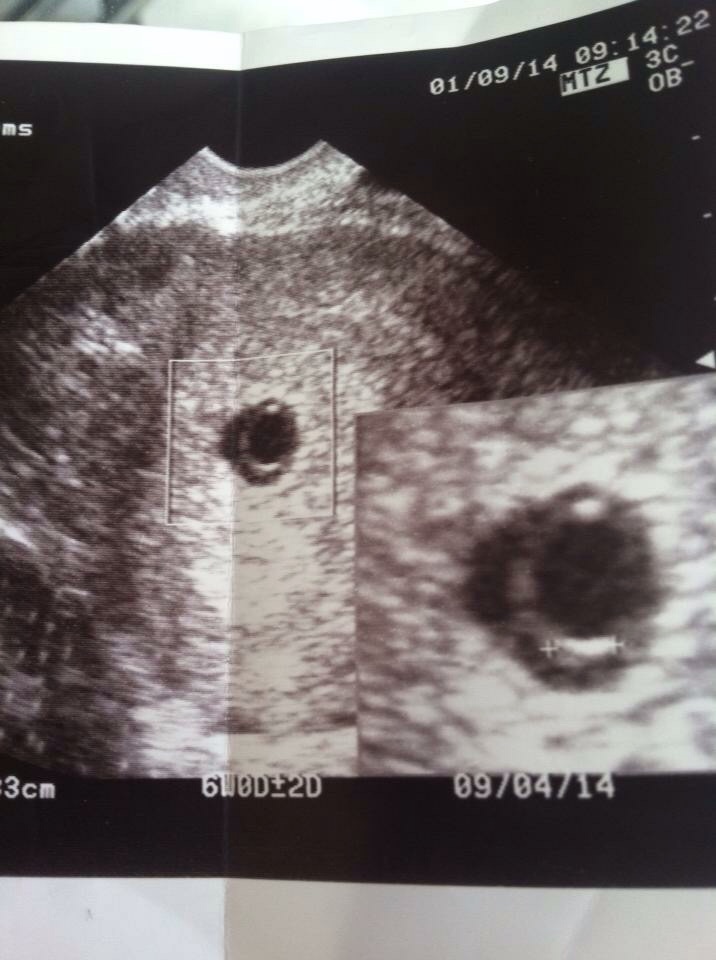

Does anyone have anything that they hold on to or look at to remind them of their miscarriage? I know it's an odd question but although my baby only made it to 7 weeks last year I still felt an attachment and loss. I have a tattoo and I kept my ultrasound . (Tattoo is an angel winged turtle on my leg)

• Yes I kept the ultrasound picture of the baby I lost last year.

• For a long time I didn't want to look at it but now it's a bit more comforting.